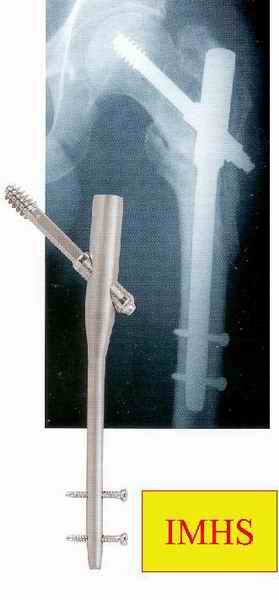

слайды:

Long TFN

Short TFN

IMHS

DePuy Trochanteric Nail

Контролировать варус